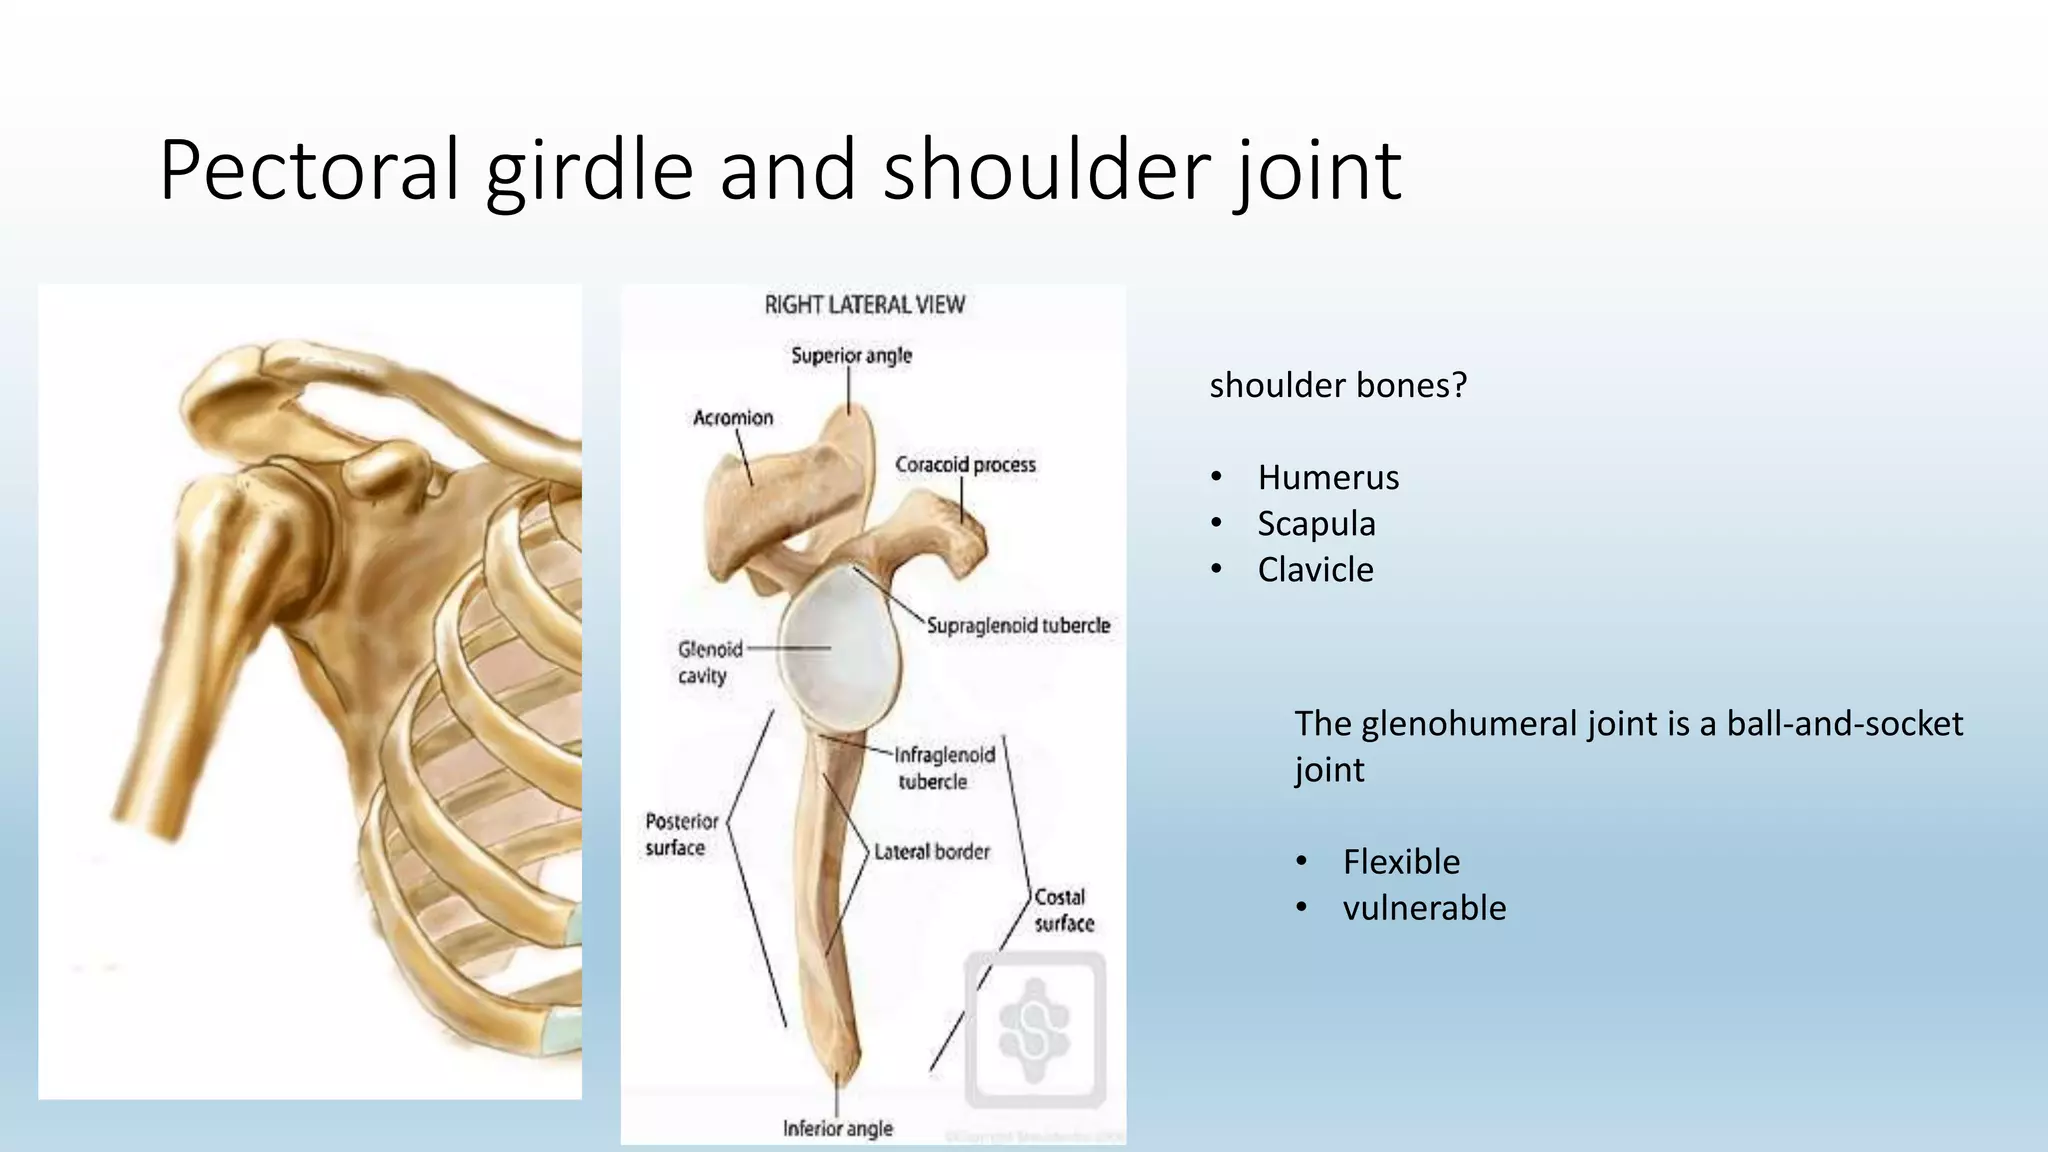

The document summarizes an anatomy revision session on the upper limb. It discusses various muscles of the upper limb including their origins, insertions, innervations and functions. Key muscles covered include the pectoralis major and minor, serratus anterior, deltoid, biceps brachii, brachialis, coracobrachialis, and triceps. It also discusses the rotator cuff muscles and muscles of the forearm including flexor carpi ulnaris and radialis. The session aims to help students identify upper limb muscles and understand their relations to nerves.